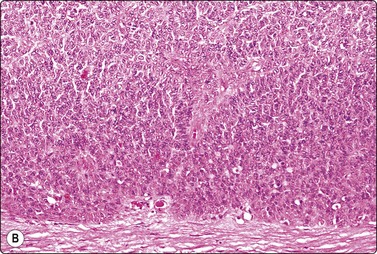

Seminoma (Figs 13.30 and 13.31)14,50,57-63,65,66

image image

Fig. 13.30 Seminoma

(A) Dispersed cells with large pale nuclei and poorly defined cytoplasm; note ‘tigroid’ background, smudged nuclei and small lymphocytes (MGG, HP); (B) Dispersed cells; moderately pleomorphic vesicular nuclei; single or multiple prominent nucleoli; many scattered lymphocytes (Pap, HP).

image

Criteria for diagnosis

Cell-rich smears,

Dispersed cells, little tendency to clustering,

Highly fragile cytoplasm and nuclei (’tigroid background’ (TB) and nuclear trailing),

Large rounded vesicular nuclei; distinct nucleoli, smaller than in embryonal carcinoma,

Irregular chromatin with some clearing,

Abundant fragile, pale/clear cytoplasm; some marginal vacuoles (punched-out vacuoles),

Lymphocytes, plasma cells,

Tangled chromatin threads (seminoma cells and lymphocytes),

Some epithelioid histiocytes, epithelioid granulomas (variable),

Striking contrast in size between seminoma cells and the background of lymphocytes and plasma cells.

Immunocytochemistry: cells positive for PLAP, c-kit (CD117) and OCT 3/4, and negative for CD30, AE1/AE3, and CK7, CK8, CK18 and CK19, although focal pancytokeratin-positive cells may be seen.

Seminoma is a highly cellular neoplasm of poorly cohesive cells and little stroma. The presence of a lace-like tigroid background (TB), and the high cellularity including lymphocytes account for the intense navy-blue color of the smears. This may suggest the diagnosis even before microscopic study. Comments about the origin of TB and the distinction from ‘lymphoglandular bodies’ have been made elsewhere.60 TB may go unnoticed in Pap-stained smears, but is more conspicuous in DQ smears (Fig. 13.30). A diagnosis of seminoma should not be based solely on the presence of TB or TB-like material. We have observed TB-like material also in aspirates of embryonal carcinoma. The contrary is also true: seminoma should not be ruled out simply because the pathologist is unable to identify TB.14 Large seminomas may show prominent necrosis. Necrosis is a major cause of false negatives in testicular FNA.59 Tumor giant cells or syncytiotrophoblastic cells may be seen in aspirates of seminoma, but can also be found in embryonal carcinoma, mixed TGCT and in trophoblastic tumors.

The plasmatic membrane is well-defined in seminoma, but it is difficult to see in embryonal carcinoma. When lymphocytes, plasma cells, histiocytes and epithelioid granulomas are abundant and seminoma cells scarce, a diagnosis of granulomatous orchitis may be entertained: the absence of spermatozoids and of the germinal line suggest a seminoma.60

Chromatin trailing may be prominent, particularly if the sample was smeared vigorously. This artifact has no diagnostic value in itself, since it may occur also in embryonal carcinoma, yolk sac tumors, lymphomas and acute orchitis. When the smear is dominated by this artifact, and there are no acute inflammatory cells and no spermatogenesis, the pathologist must search carefully for preserved diagnostic cells. In this situation, a tentative diagnosis of seminoma may be made.14

Lymphocytes, plasma cells and even ‘lymphoglandular bodies’ may be prominent in smears of seminoma and may lead to an erroneous diagnosis of lymphoma. Lymphoblasts may also be mistaken for seminoma cells.

Familiarity with the cytology of testicular seminoma helps in the recognition of extragonadal seminoma and metastatic seminomas (Fig. 13.31). Immunostaining may be of help in doubtful cases.69